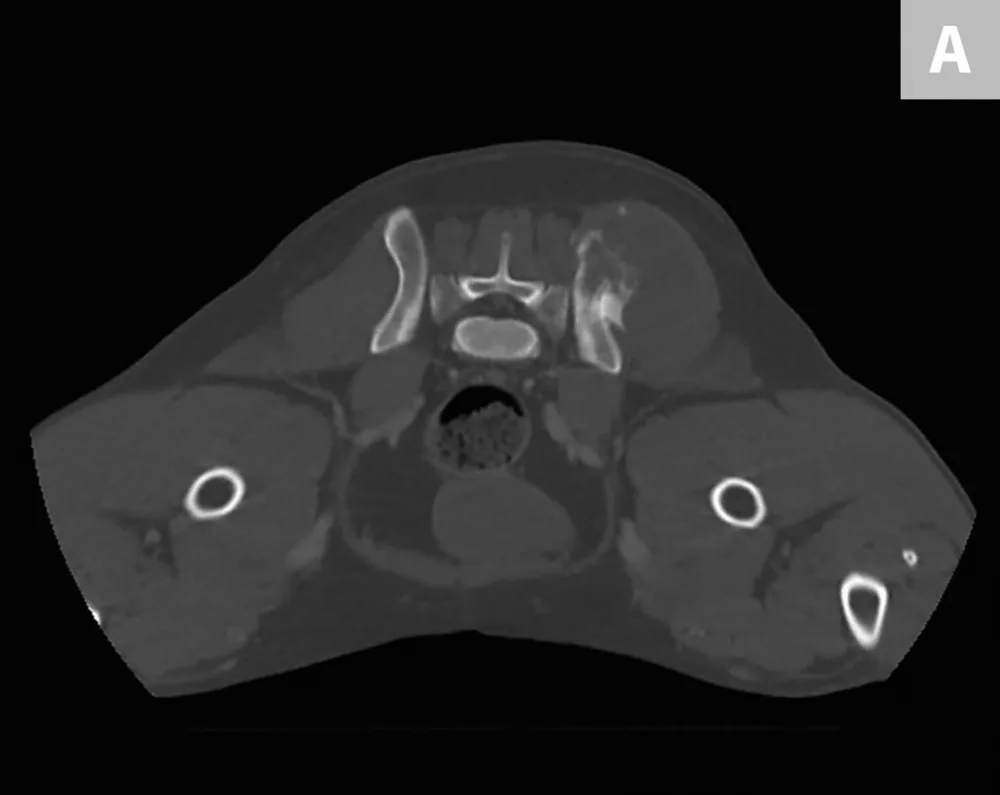

FIGURE 2

Bone scan image from the patient. Increased uptake of radiopharmaceutical in the left ilium (arrow) and a potential lesion in the left costal cartilage (oval) can be noted.

Diagnosis

CBC, serum chemistry profile, and urinalysis results were unremarkable. Three-view thoracic radiographs showed no evidence of gross metastatic disease. A CT scan of the chest, abdomen, and pelvis showed an aggressive bone lesion of the left ilium, compatible with osteosarcoma, with tumor extension to the surrounding soft tissue (Figure 1). A full-body bone scan was performed. Static images were obtained 2 hours after intravenous injection of Tc99m-MDP. There was marked uptake in the area of the primary tumor (ie, the left ilium). There was also a possible metastatic lesion in the left costal cartilages; however, careful review of the CT scan showed that the increased uptake of radiopharmaceutical at that site was most likely consistent with old trauma rather than metastatic disease (Figure 2).